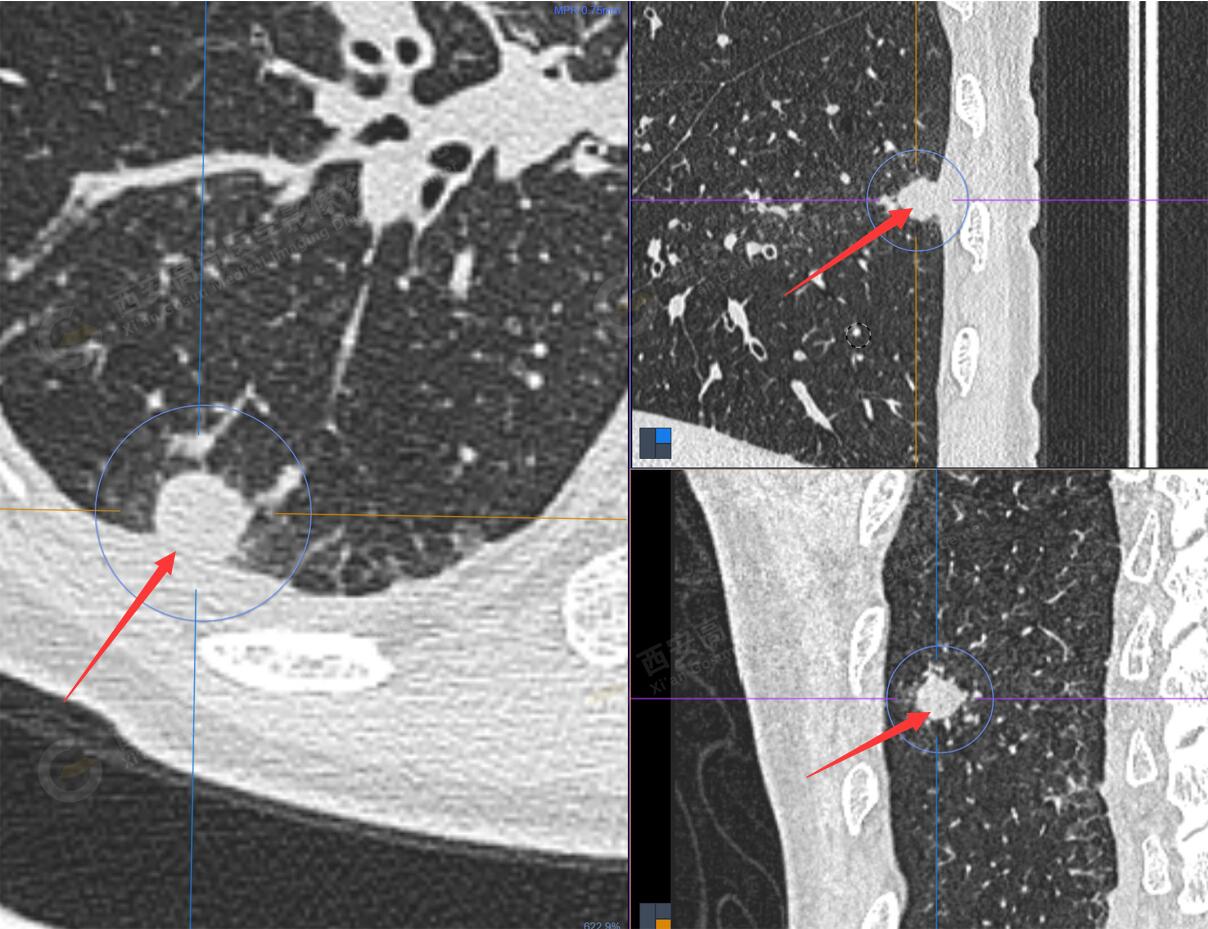

1.右肺下葉后基底段軟組織結(jié)節(jié)(約1.5cm×1.2cm),與相鄰后胸膜分界不清,呈FDG代謝異常增高,結(jié)合病理,符合肺腺癌伴鄰近胸膜侵犯。

2.雙肺多發(fā)高密度小結(jié)節(jié)灶(最大徑約0.7cm),部分較大結(jié)節(jié)呈FDG代謝略增高,均考慮為轉(zhuǎn)移性病變。